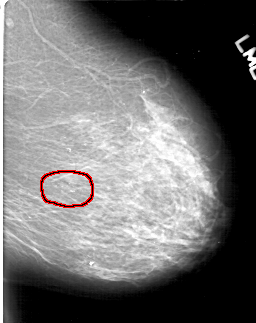

D_4198_1.LEFT_CC

LEFT_CC LINES 6571 PIXELS_PER_LINE 4351 BITS_PER_PIXEL 12 RESOLUTION 43.5 OVERLAY

FILE: D_4198_1.LEFT_CC.OVERLAY

TOTAL_ABNORMALITIES 1

ABNORMALITY 1

LESION_TYPE CALCIFICATION TYPE ROUND_AND_REGULAR-PLEOMORPHIC DISTRIBUTION CLUSTERED

ASSESSMENT 0

SUBTLETY 4

PATHOLOGY BENIGN

TOTAL_OUTLINES 1

BOUNDARY